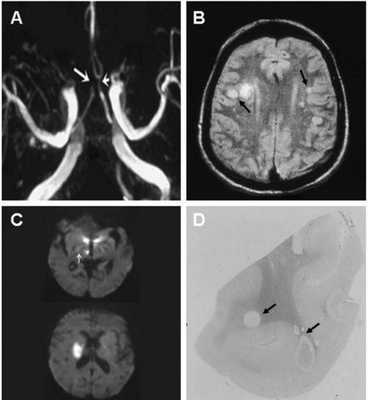

(А) времяпролетная МР-ангиограмма демонстрирует расширение левой (короткая стрелка) и окклюзию просвета правой (длинная стрелка) передних мозговых артерий

(В) МР-скан головного мозга определяет множественные гиперинтенсивные области в обеих гемисферах, в основном локализованные в белом и на границе серого и белого вещества (стрелки).

(С) При использовании последовательности DWI определяются участи ограничения диффузии (что отвечает ишемии) в таламусе, гипотоламусах и задней части внутренней капсулы справа (стрелка). Неделю спустя у пациента развилась картина гемиплегии.

(D) Макроскопические изменения у пациента, умершего в результате хронической васкулопатии. Овоидной формы множественные участки ишемии и демиелинизации.